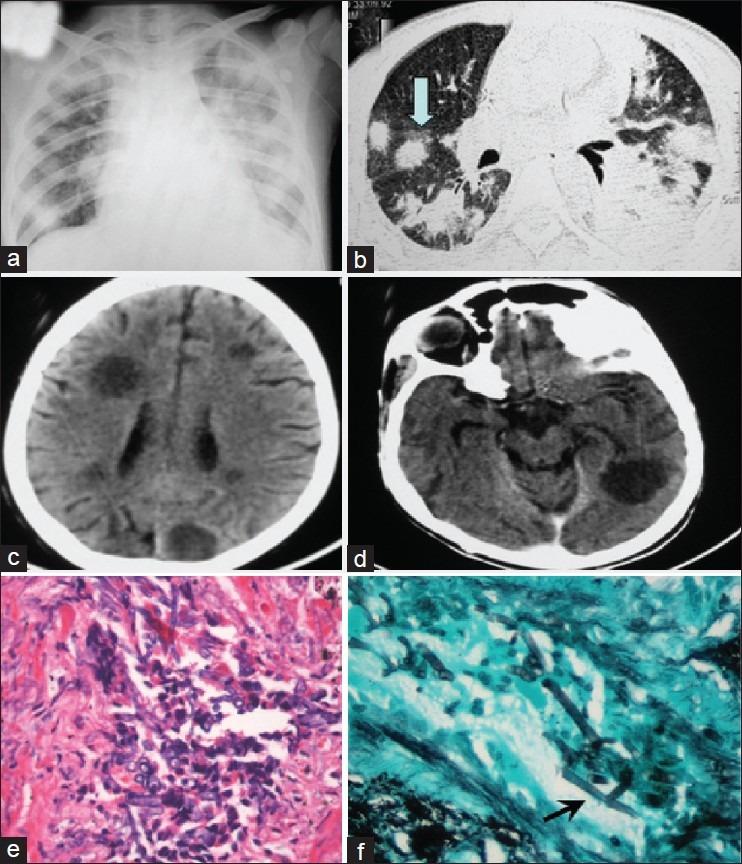

Angioinvasive pulmonary infection from filamentous fungi is not an uncommon occurrence in immunocompromised patients like acute lymphoblastic leukemia (ALL). Rarely, these lesions can spread via the hematogenous route and involve multiple visceral organs. We report a case of a 14-year-old boy with ALL who developed angioinvasive pulmonary aspergillosis early in the course of induction therapy, which was followed by hematogenous dissemination and formation of multiple brain abscesses. The patient was treated with intravenous amphotericin B. There was no response to the therapy and the patient succumbed to disseminated infection. Postmortem lung biopsy confirmed angioinvasive pulmonary aspergillosis. Poor penetration of amphotericin B across the blood-brain barrier could be one of the contributory factors for poor response to antifungal therapy. We discuss the various antifungal agents with respect to their penetration in brain.

在免疫功能低下的患者如急性淋巴细胞白血病(ALL)中,丝状真菌引起的血管侵袭性肺部感染并不少见。这些病变很少通过血行途径扩散并累及多个内脏器官。我们报告一例14岁患ALL的男孩,在诱导治疗早期发生了血管侵袭性肺曲霉病,随后出现血行播散并形成多个脑脓肿。该患者接受了静脉注射两性霉素B治疗。治疗无效,患者死于播散性感染。尸检肺活检证实为血管侵袭性肺曲霉病。两性霉素B透过血脑屏障的能力差可能是抗真菌治疗效果不佳的一个促成因素。我们讨论了各种抗真菌药物在脑内的渗透情况。